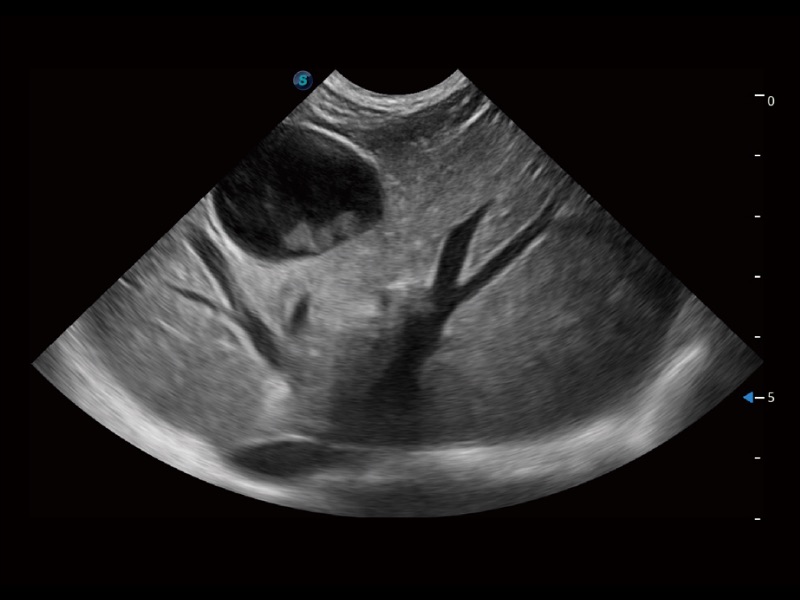

优异的基础图像

(犬)肝脏